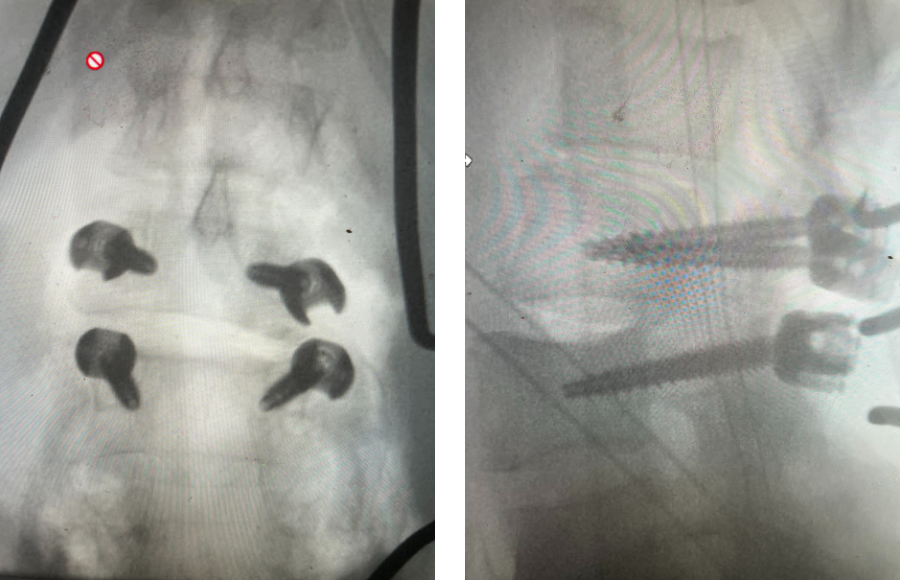

Fig 1: Plain X-rays demonstrating a grade 1 L45 spondylolisthesis with dynamic translation of approximately 4 mm (arrow).

Plain lumbar x-rays were done with flexion/extension views. Surprisingly the patient had 4 mm of anterior translation and slight angulation in flexion (Fig 1). This was unexpected because in degenerative spondylolisthesis the patient more commonly has auto stabilized by formation of stabilizing arthritic structures and has no motion on dynamic x-rays. However, approximately 20% of patients will have some degree of translation on flexion-extension x-rays with degenerative L4-5 spondylolisthesis. Because she had failed all means of conservative management, it was felt that the patient would benefit by a lumbar decompression and instrumented fusion because of the acute instability demonstrated on x-rays and her age.